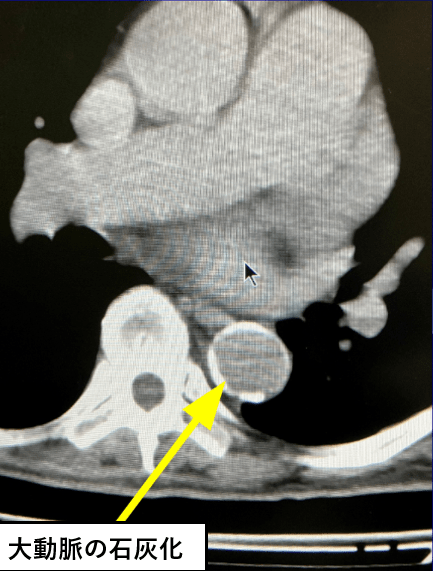

さて、突然死を防ぐ検査として前回、胸部レントゲン検査を行うと、大動脈解離や心疾患、脳卒中の発症リスクが高まる「大動脈石灰化」を見つけられることがあるとお伝えしました。

大きい瘤であれば、「胸部大動脈瘤」も胸部レントゲン検査で発見できることがあります。

高血圧症や脂質異常症、糖尿病などの動脈硬化の危険因子をもつ人は、健康診断や人間ドックの際に胸部レントゲン検査の撮影を「正面」と「側面」の2方向でしてもらうといいでしょう。

ちなみにオプションでCTをつければ、狭心症に関係する冠動